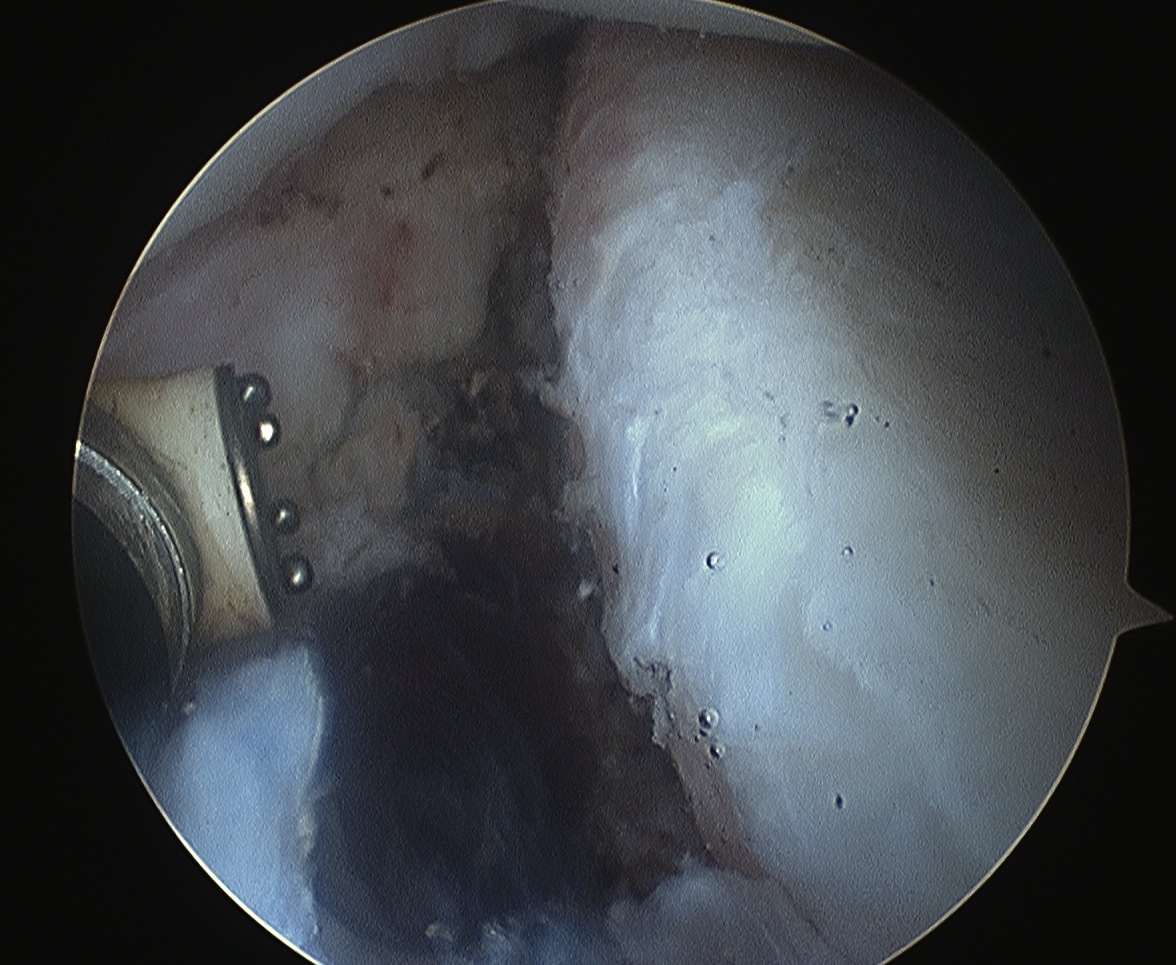

Technique arthroscopic anterior labral / Bankart repair

Steps

Mobilize anterior labrum

Debride anterior glenoid to bleeding bone

Mobilize labrum

Labral mobiliser / rasp

- labral tear can be obvious, but may have partially healed or healed medially

- change camera to anterosuperior portal for better view

- mobilize until can see subscapularis muscle underneath

- need to be able to advance labrum medially and superiorly for repair

Debride anterior glenoid bone to bleeding bone